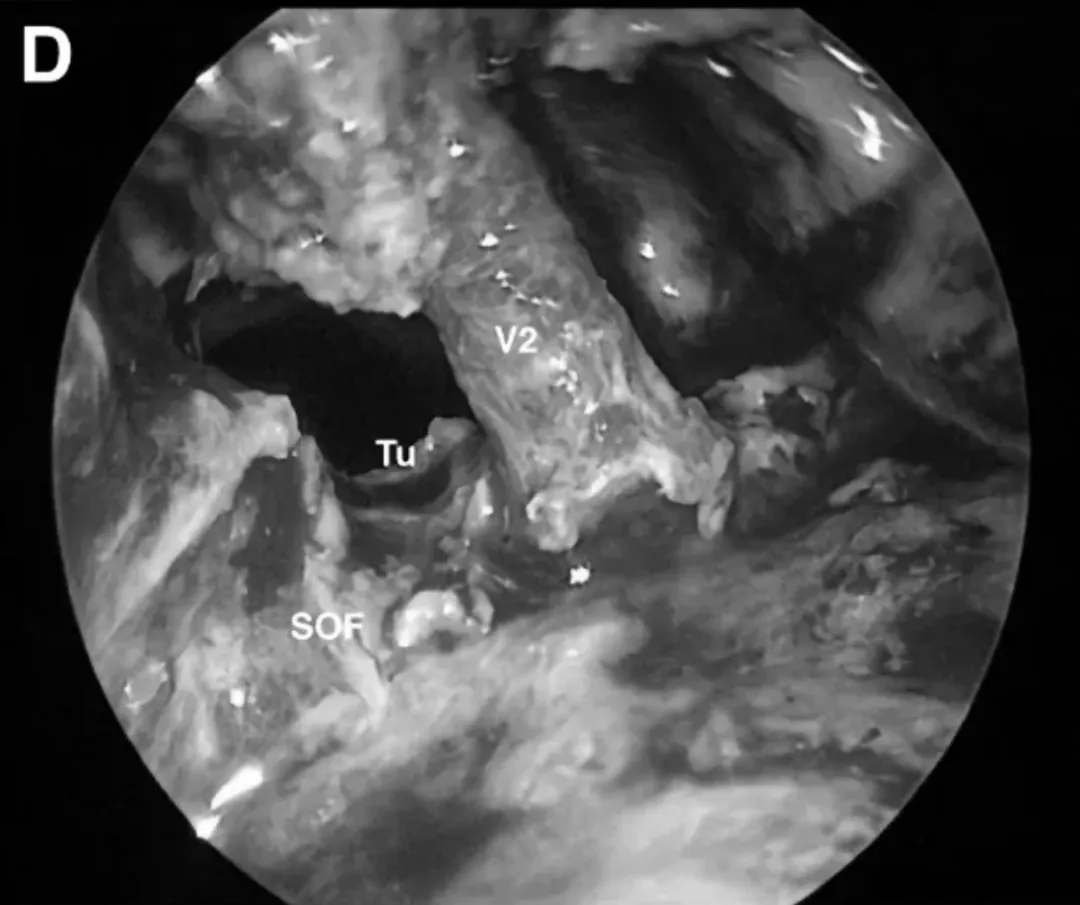

蝶窦可见肿瘤,进行充分暴露,并切除脑膜瘤。暴露眶翼腭走廊(OPC),通过上颌窦上方的眶上裂(SOF)切开PPF后部,并将PPF内容物转位至下方。取出眶壁,将眶内容物抬高,在眶下裂(IOF)内侧钻孔磨骨,进入蝶窦,完成蝶窦肿瘤的镜下全切。

内镜下术中视图显示前内侧三角(AMT)和OPC增大。使用30°角的内窥镜检查蝶窦内是否存有残留的任何肿瘤。

SphS蝶窦的内镜视图。使用颞肌封闭蝶窦SphS,并用明胶海绵和纤维蛋白胶封闭。